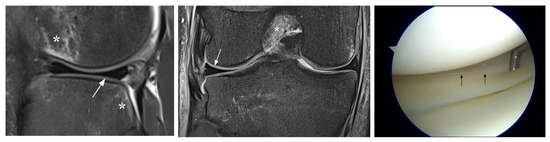

| Equivocal | ||||||

| FN MM | ||||||

| 21 | F, 56 y | 5 | grade 2 posterior horn | tear posterior horn | PM | |

| 14 | M, 28 y | 8 | grade 2–3 posterior horn | undersurface tear posterior horn | acute | R |

| 22 | M, 40 y | 74 | grade 2 posterior horn | degenerative tear posterior horn | PM | |

| 23 | M, 48 y | 7 | grade 2–3 posterior horn | large tear posterior horn | acute | PM |

| 24 | M, 31 y | 7 | grade 2 posterior horn | undersurface tear posterior horn | acute | R |

| 25 | F, 40 y | 7 | grade 2–3 posterior horn PO remnant | undersurface tear posterior horn PO remnant | acute | PM |

| 26 | F, 44 y | 9 | grade 2–3 posterior horn | undersurface tear posterior horn | acute | PM |

| FN LM | ||||||

| 27 | F, 32 | 47 | grade 2 anterior horn with parameniscal cyst | tear anterior horn | PM | |

| 28 | F, 52 | 34 | grade 2 anterior horn | tear anterior horn | PM | |

| 29 | F, 18 | 80 | grade 2 posterior horn | undersurface tear posterior horn | R | |

| 10 | M, 25 | 11 | grade 2–3 posterior horn | small tear body posterior horn | acute | PM |

| FP MM | ||||||

| 30 | F, 51 y | 27 | grade 2–3 posterior horn PO remnant | intact PO remnant | ||

| 31 | M, 70 y | 70 | grade 2–3 posterior horn | normal | ||

| 32 | F, 24 y | 23 | equivocal ramp lesion posterior horn | normal | acute ACL | |

| FP LM | ||||||

| 30 | F, 51 | 27 | grade 2 posterior horn | normal | ||